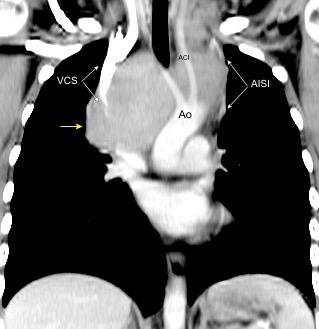

Síntomas y signos que se producen con la obstrucción total o parcial de la vena cava superior

Causas Malignas +/- 90-95%

Ca. Broncogénico (80-85%)

Linfoma No Hodgkin (15%)

Catéteres, shunts y marcapasos…23%

T. Mediastínico. Bocio

Fibrosis Idiopática

Tb, Histoplasmosis, Actinomicosis, Sarcoidosis

Grupos:

1. Obstrucción por encima de la V Ácigos. (La sangre llega al corazón a través de ella)

2. Obstrucción con participación de la V. Ácigos. (La sangre utiliza otras alternativas para llegar al corazón vía VCI).

Participación de la V. Ácigos como vía principal para llegar a la VCI.

Visible: 88%

Depresión ligera…….55% profunda. 35%